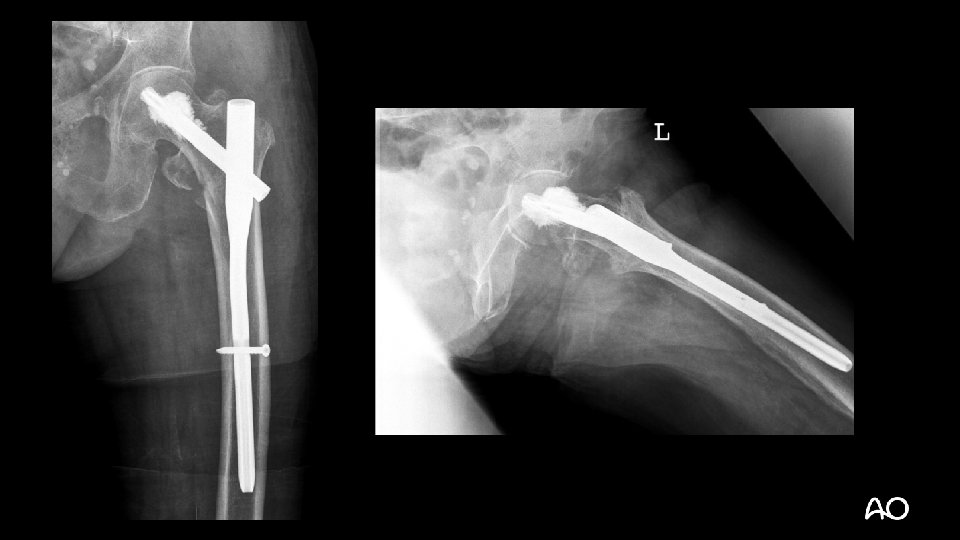

Treatment • Cleared for surgery within 8 hours • PFNA • General anesthesia

1 -year follow-up